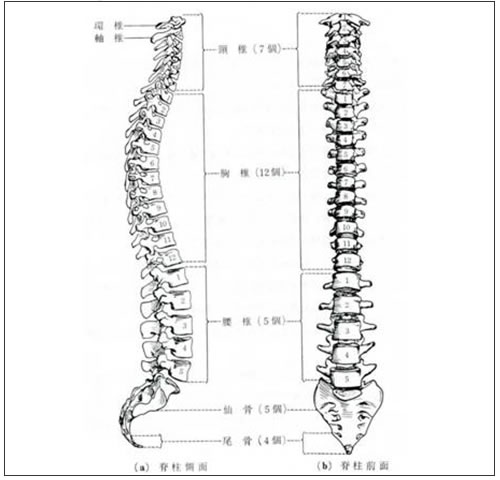

JUGEMテーマ:接骨院・整骨院 人間の背骨は起立歩行に適するように有利な形に変形しています。この変形を生理的脊柱湾曲といいます。生理的彎曲は4つあり、頸部前彎、胸部後彎、腰部前彎、仙骨部後彎となります。この形を維持するようにすればほとんどの腰痛は防げると言われています。 私は頚部前弯がなく、いわゆるストレートネックです。さらに11年前に交通事故に遭い、レントゲン検査で腰部前弯もないということが判明しました。事故のけがは、むち打ち症ということで軽傷で済みましたが事故...